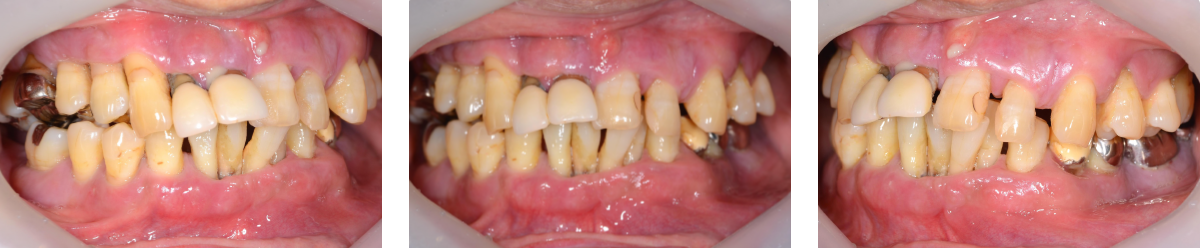

初診時の状態

歯周病により歯はグラグラの状態で、元の位置から動いてしまっていました。

また、レントゲン写真でも歯を支えている骨が吸収していることが明らかで、噛む力を十分に支えられない状態でした。

このままの状態で歯を残すことは難しく、抜歯が必要と判断しました。

初診時口腔内写真